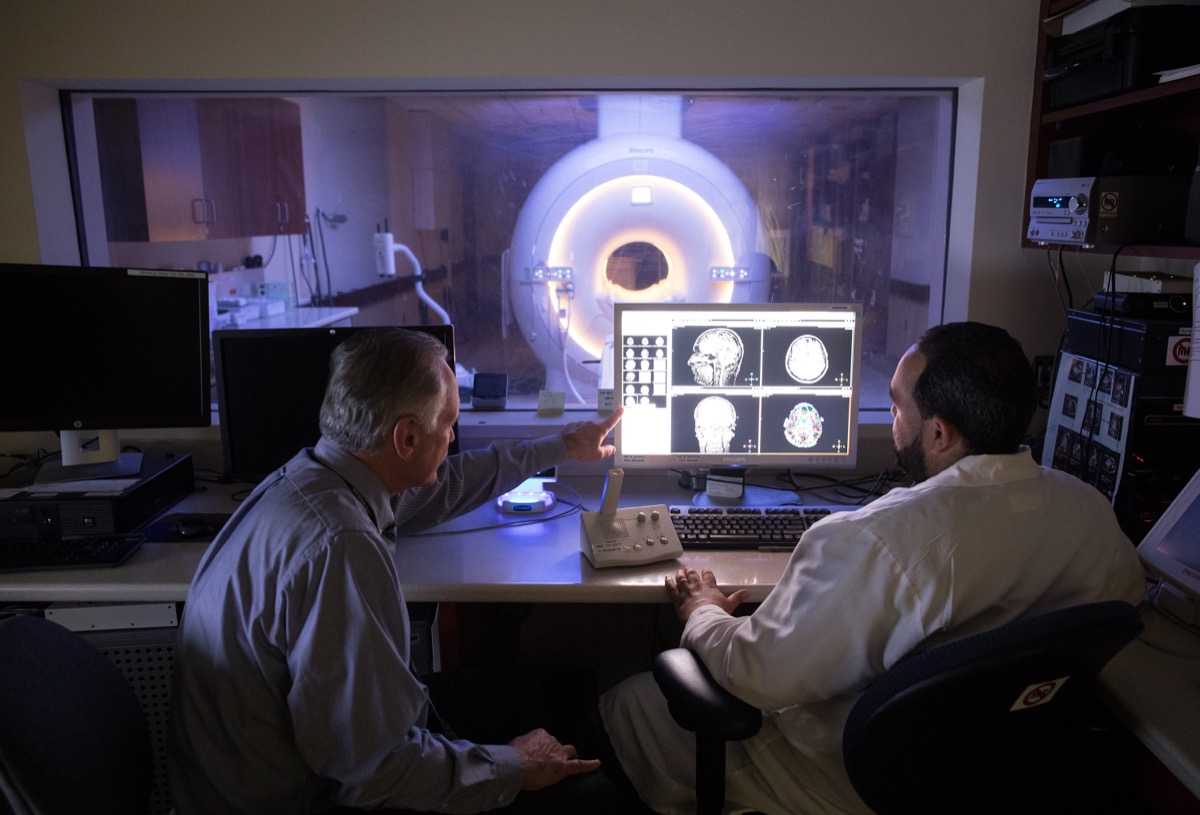

We prepare our residents for their careers as physicians with a training that emphasizes hands-on teaching and graded independence. Our Diagnostic Radiology Residents learn to dictate cases independently through apprentice-style teaching at the workstation and an extensive didactic teaching curriculum, while our Integrated Interventional Radiology Residents gain valuable clinical experience by practicing in multiple environments and managing patient care. Each resident sees a high volume of cases, including severe cases in our NCI Cancer Center and Liver Transplant Program. Specialty collaboration, direct feedback, collegiality and research opportunities allow every resident to maximize their potential.

Moses Campus is the primary teaching site for our training programs. Our sub-specialty reading rooms serve as a hub for active clinical care and teaching, and support tertiary-level referral programs throughout the entire breadth of adult and pediatric medicine. In addition to specialized reading rooms, residents have full access to our resident library and a newly renovated resident lounge, and are invited to take advantage of our 3D imaging lab. Resident conferences are presented in-person from Binswanger Auditorium, although we electronically simulcast lectures and conferences from Moses to all our clinical sites. Resident learning is enhanced through participation in a range of interdisciplinary tumor boards and research programs.

On the East Campus, the Jack D. Weiler Hospital is the central hub where Montefiore Einstein Radiology Residents experience hands-on training in an academic community hospital setting. The hospital’s location at the Albert Einstein College of Medicine Campus allows fellows to work directly with faculty and develop independence through hands-on-training. Weiler is also home to the Albert Einstein Cancer Center, which provides extensive case material for clinical cases and highlights multiple interdisciplinary conferences. Residents work directly with faculty on the Interventional Radiology (IR) service and take independent calls as senior residents from Einstein, enhancing their learning and independent clinical practice. The East Campus is also home to the PET Imaging Center, a dedicated Nuclear Medicine outpatient facility, and the nearby Comprehensive Breast Cancer Care Center.